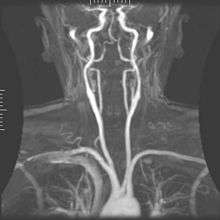

Magnetic resonance angiography

Magnetic resonance angiography (MRA) generates pictures of the arteries to evaluate them for stenosis (abnormal narrowing) or aneurysms (vessel wall dilatations, at risk of rupture). MRA is often used to evaluate the arteries of the neck and brain, the thoracic and abdominal aorta, the renal arteries, and the legs (called a "run-off"). A variety of techniques can be used to generate the pictures, such as administration of a paramagnetic contrast agent (gadolinium) or using a technique known as "flow-related enhancement" (e.g., 2D and 3D time-of-flight sequences), where most of the signal on an image is due to blood that recently moved into that plane, see also FLASH MRI. Techniques involving phase accumulation (known as phase contrast angiography) can also be used to generate flow velocity maps easily and accurately. Magnetic resonance venography (MRV) is a similar procedure that is used to image veins. In this method, the tissue is now excited inferiorly, while the signal is gathered in the plane immediately superior to the excitation plane—thus imaging the venous blood that recently moved from the excited plane.[165]